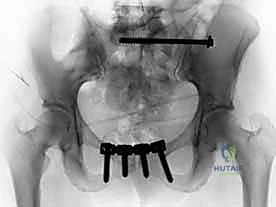

بمجرد عودة العظام إلى مكانها الصحيح، يتم تثبيتها بشكل دائم باستخدام مواد طبية متوافقة حيوياً (عادة من التيتانيوم). تشمل هذه المواد:

* الشرائح المعدنية (Plates): توضع على سطح العظم لتعمل كجسر داعم.

* المسامير الطبية (Screws): تُثبت الشرائح بالعظم، وتُستخدم أحياناً مسامير طويلة (Iliosacral Screws) لربط عظم الحرقفة بالعجز لضمان استقرار المفصل.

يتم الاستعانة بجهاز الأشعة السينية المتحرك داخل غرفة العمليات (C-arm Fluoroscopy) للتأكد من وضعية المسامير بدقة المليمتر، لضمان عدم اختراقها للأعصاب أو الأوعية الدموية.